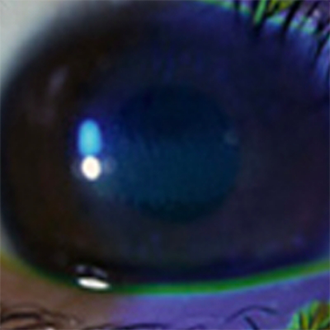

角膜上皮障害

- 眼の角膜(黒目に当たる部分を被っている膜)の表層部分の障害です。

コンタクトレンズ装用によって起きることが多く、乾燥や酸素不足、レンズの汚れ、眼に合わないレンズの装用などが原因で起こります。 - そのまま放っておくと角膜潰瘍になり、細菌感染が原因で最悪の場合は失明することも場合もあるので、早期発見・早期治療が大切です。

- コンタクトレンズ装用中に眼がゴロゴロとする感じや痛みを感じたら、かかっている可能性があります。早期治療をすれば傷をきれいに治すことができますので、このような症状の時には、すぐ眼科専門医の診断を受けて下さい。初期段階では、自覚症状がないので、定期的に眼科で検査を受けるようにしましょう。(写真は点状表層角膜症:検査用に染色しています)